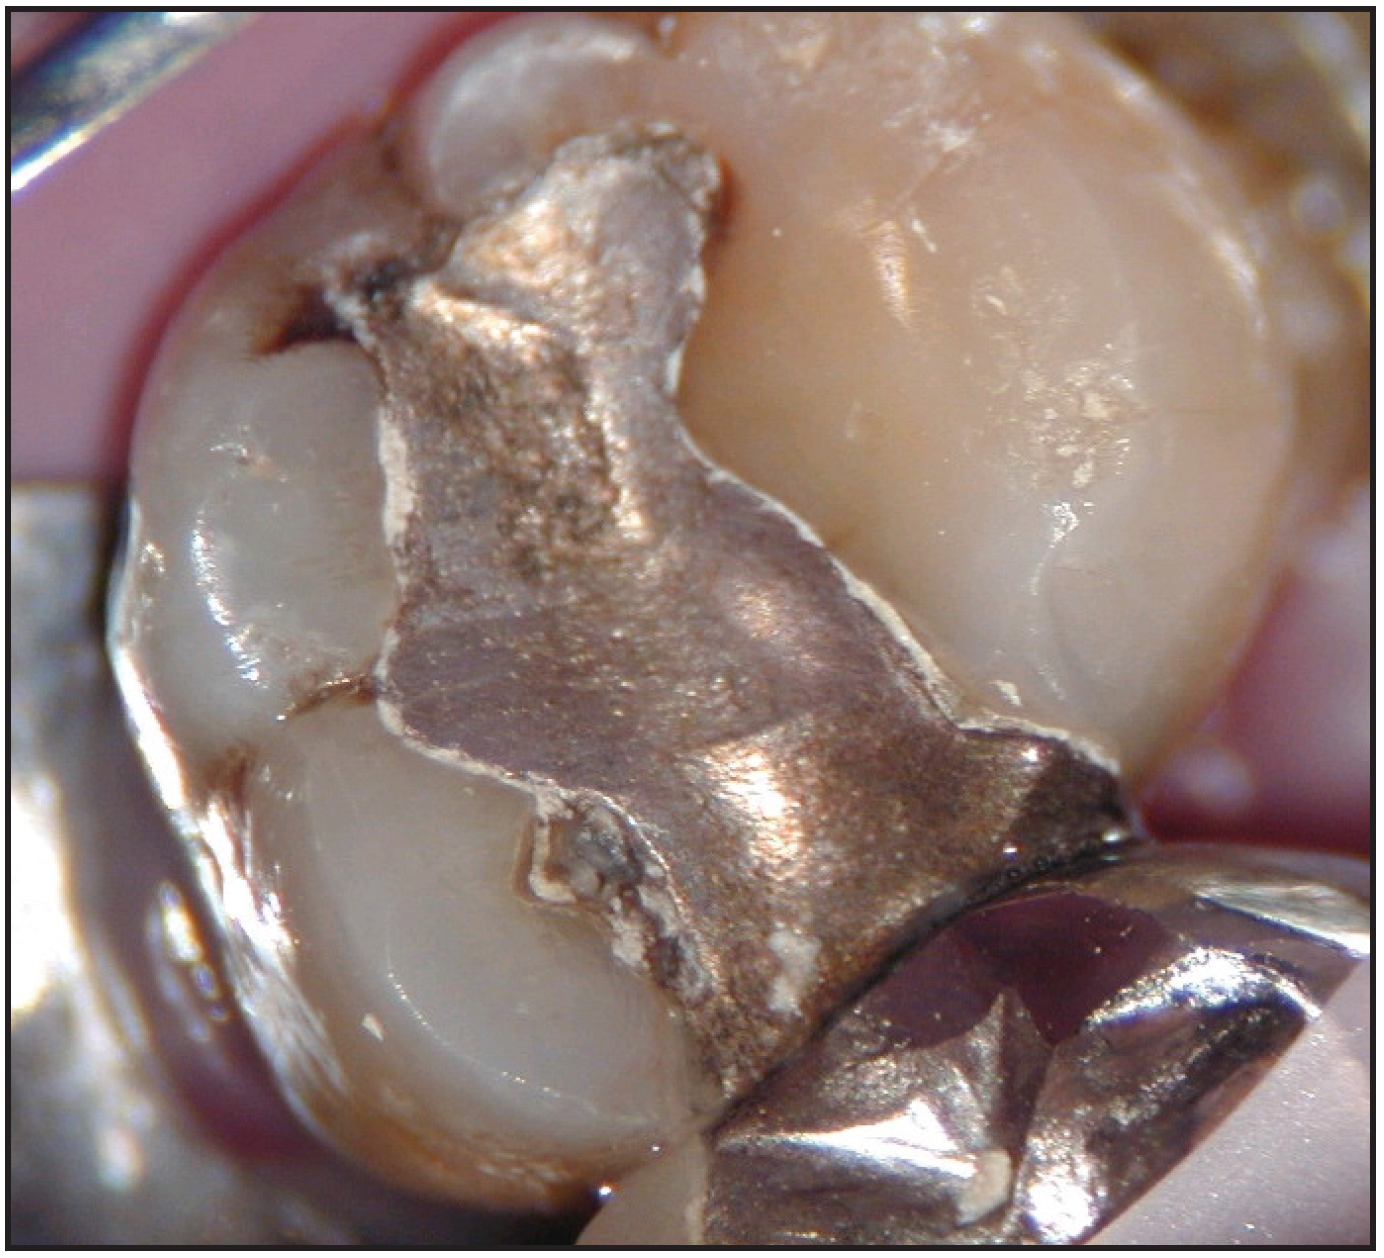

The potential ravages of soda pop caries in teenagers should not be underestimated. Some teenagers drink as many as 12 cans of soda pop a day. In one well-documented case, a teenager who grew up drinking fluoridated water and brushing twice daily with a fluoride-containing toothpaste developed caries in every one of his erupted teeth, necessitating two extractions and many restorations. Diet analysis revealed that he consumed 6-12 cans of soda pop daily.4 Some of the ravages of this condition are visible in Figure 2 and Figure 3. Other case reports have demonstrated similar findings among other adolescents in whom chronic, high soda pop consumption was linked with widespread demineralization of enamel and extensive caries in pits and fissures and in the interproximal areas.5

Figure 3 – Erosion. Courtesy of Dr. Peter Endo.

Figure 3